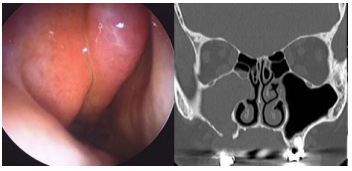

Menino, 7 anos de idade, com queixa de obstrução nasal e rinorreia posterior. Ao longo da sua vida, já foi internado por 4 vezes por pneumonias. Ao exame de endoscopia nasal, observa-se fossas nasais estreitas, pólipos nasais ocupando dois terços e secreção mucoide em ambas as fossas nasais. Imagens de tomografia dos seios da face são apresentadas a seguir:

Enunciado 4540970-1

Considerando a paciente em questão, qual dos exames abaixo confirmaria a principal hipótese diagnóstica?